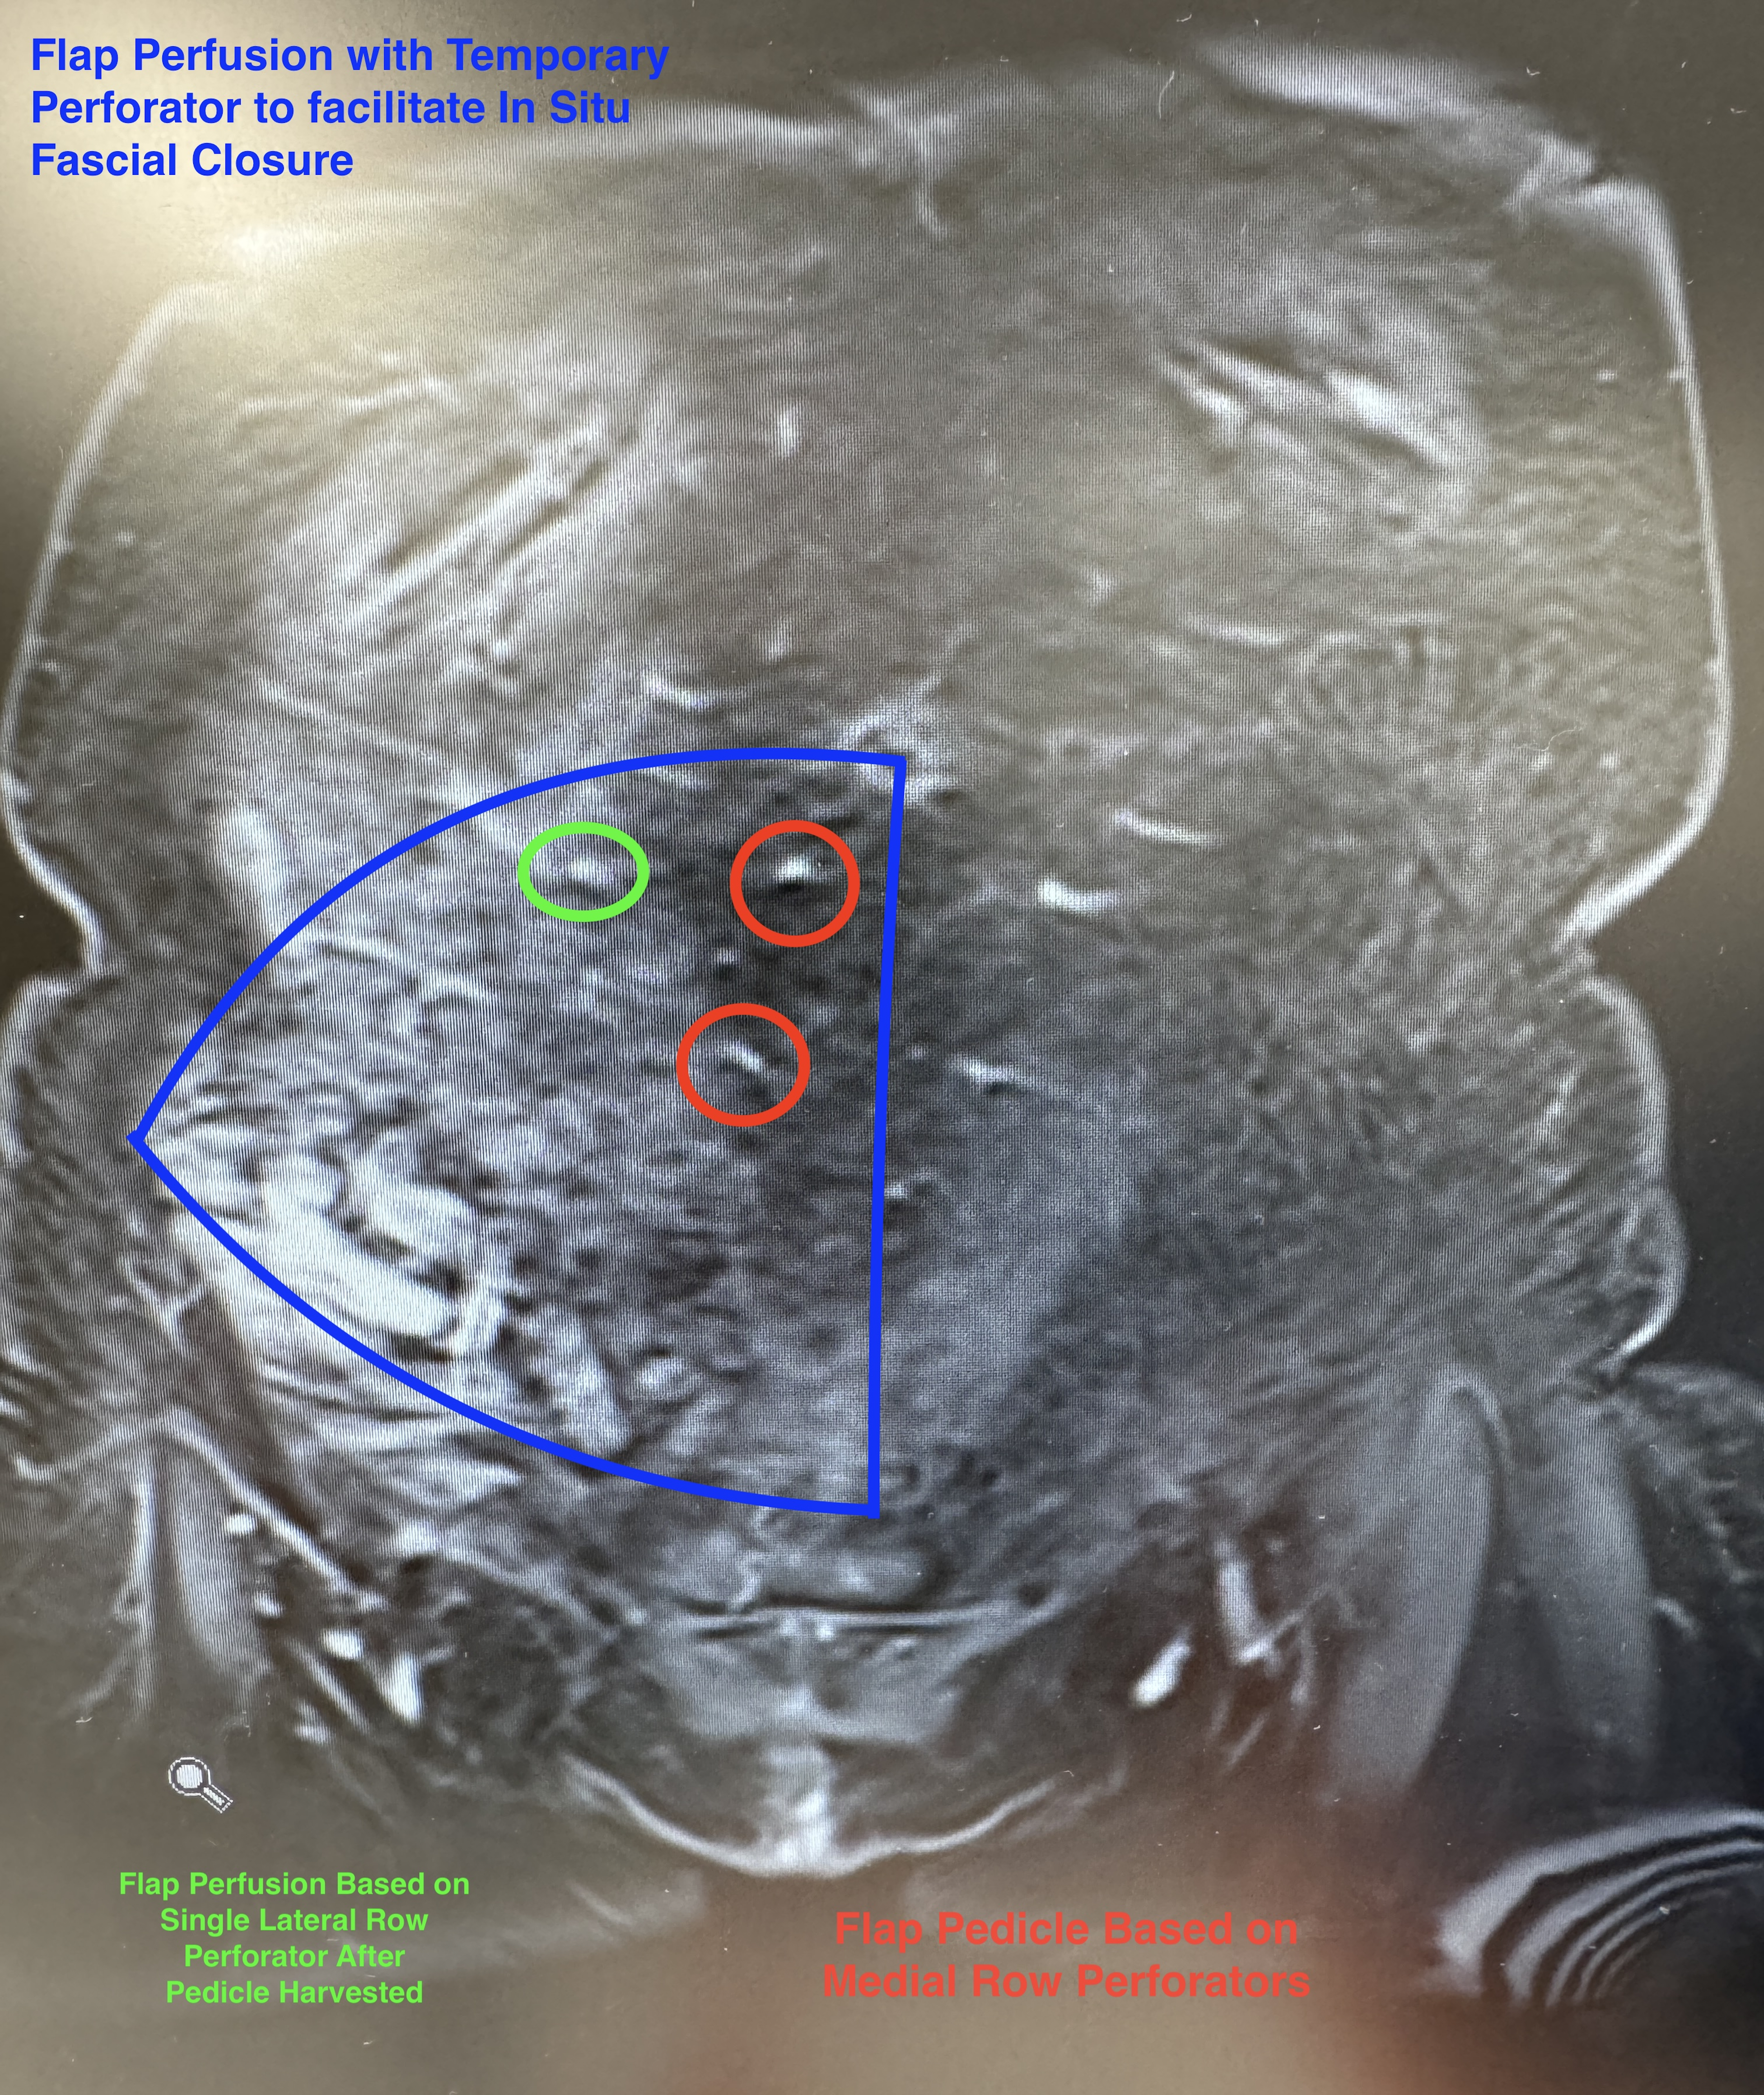

The patient was a 46-year-old woman with left breast cancer who opted for bilateral nipple-sparing mastectomy with immediate bilateral breast reconstruction using DIEP flaps. The right mastectomy was completed first, thereby allowing the contralateral left hemi-abdominal flap to be harvested and anastomosed without complication. The second (right) flap was dissected prior to completion of the left mastectomy and recipient vessel exposure. This right hemi-abdominal flap was based on medial row perforators of the deep inferior epigastric artery and vein (Figure 1). Pedicle ligation of the right hemi-abdominal flap was performed prior to the flap being ready for transfer. This flap maintained perfusion (trickle charging) with a single lateral row perforator that was no longer in continuity with the main pedicle (Figure 2). With main pedicle ligation, the preserved lateral row perforator most probably obtained its blood supply from an intercostal branch that had yet to be divided, or from its continuation with the superior epigastric system. It is also important to note that flaps based on lateral row perforators can also be perfused or trickle charged with a single medial row perforator.

Figure 1: Coronal view of magnetic resonance angiography demonstrated the medial row perforators (red) on which the right hemi-abdominal flap was based. The single lateral row perforator (green) was used to temporarily perfuse the flap (trickle charging).